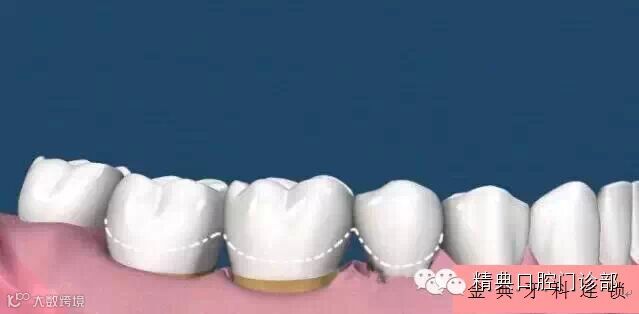

图片二十六、龈上洁治和龈下刮治之后,很多人会发现牙齿的缝隙变大了,很多人就会误解为洗牙会把缝隙洗大了。其实这是一种错误的想法,洗牙前没有感觉到牙齿的缝隙是因为那些缝隙里面填满了牙结石,舌头舔上去感觉不到,当结石清除后,缝隙就会显露出来。

图片二十七、牙周治疗结束以后牙龈会出现不同程度的退缩,有些情况这种牙龈的退缩是不可逆的。如果想防止牙龈的萎缩,唯一的办法就是半年洗一次牙齿,及时去除牙面上的牙结石,防止牙结石压迫牙龈导致牙龈的退缩。

图片二十八、这张图片显示了牙龈退缩的范围,其实牙龈的退缩和牙槽骨的吸收是相关的,牙结石的堆积导致牙槽骨的吸收,牙槽骨的吸收又会导致牙龈的退缩和牙根的暴露。所以一定要定期洗牙,预防牙周炎(中国人牙齿松动掉落,80%的原因是因为牙周炎哦)。